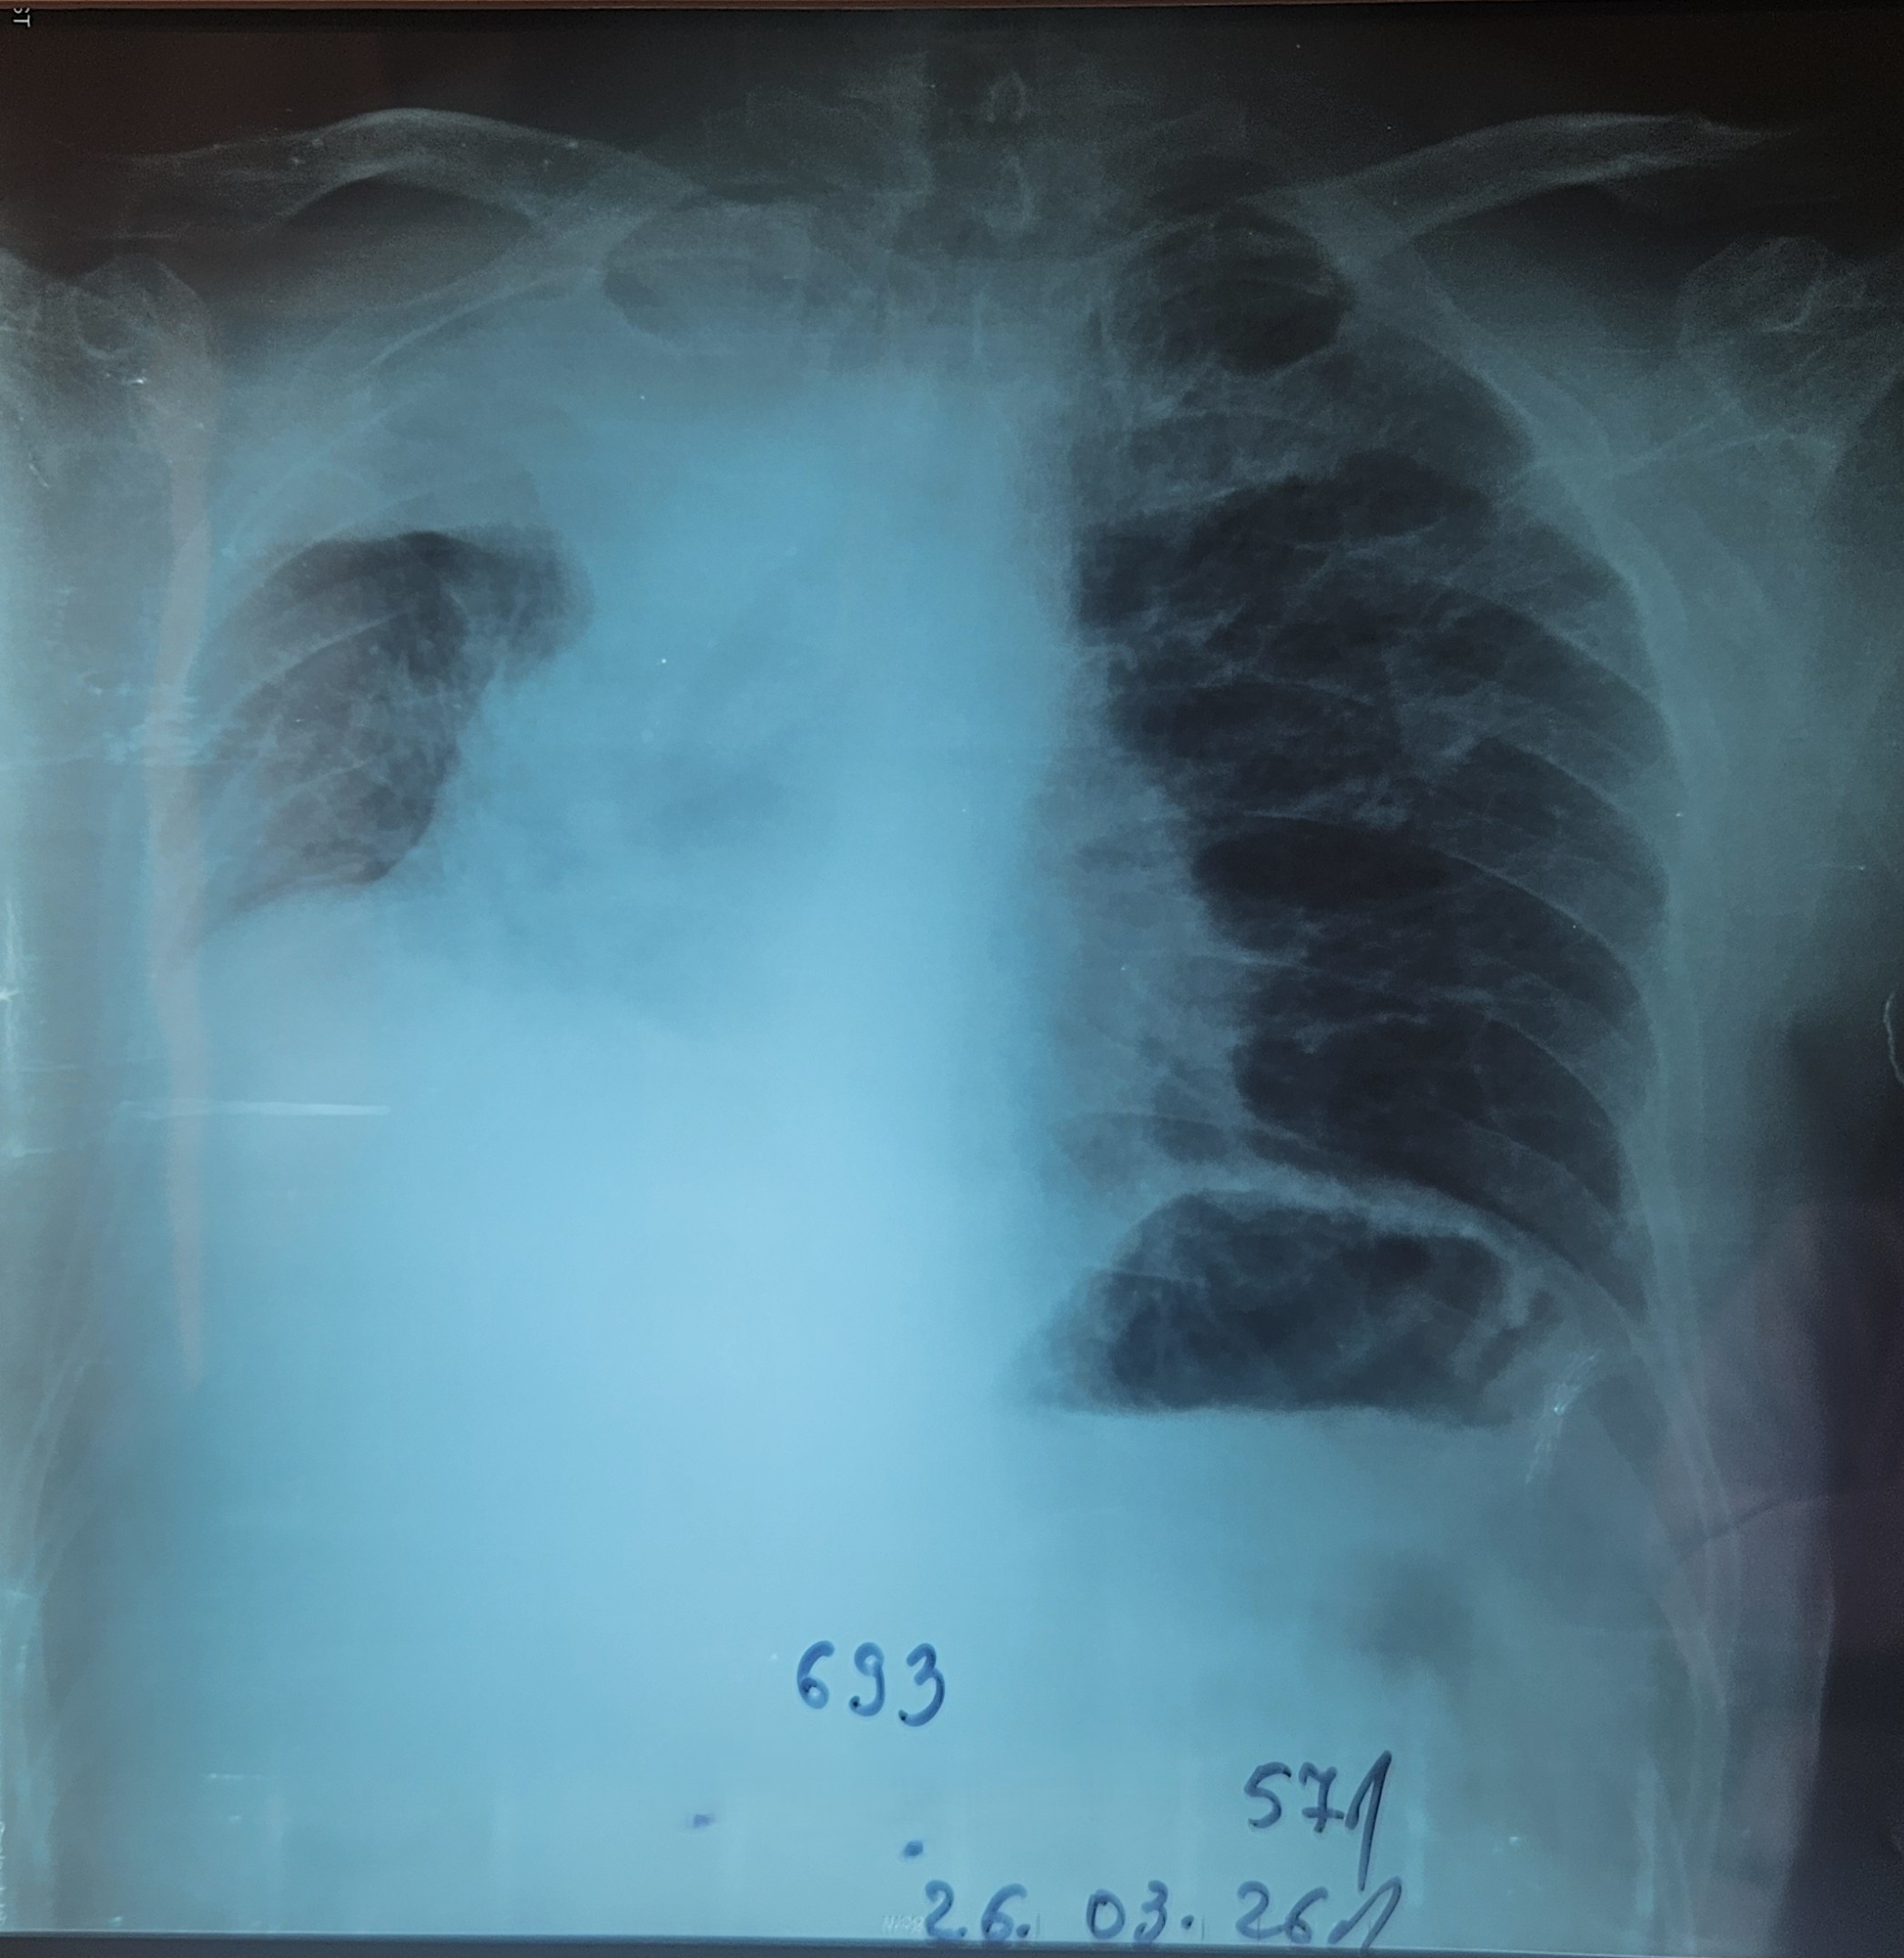

- გულმკერდის CXR სტენტირების დღეს.